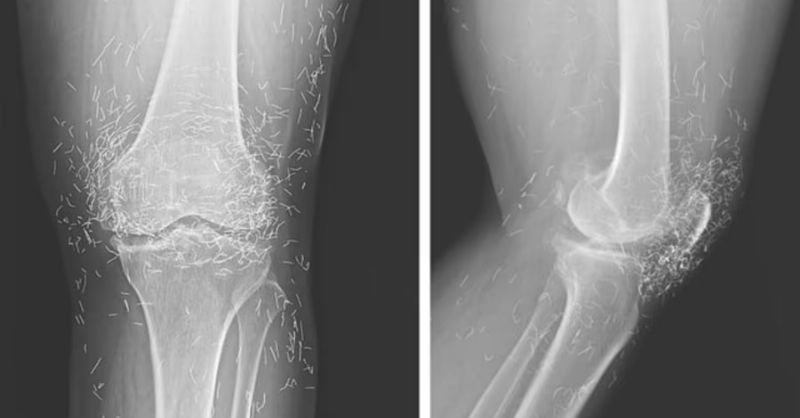

X-Ray Reveals Hundreds of Gold Needles in Woman’s Knees

Doctors in South Korea were astonished when they discovered that a 65-year-old woman’s knees were filled with hundreds of tiny gold acupuncture needles, apparently left there intentionally during...